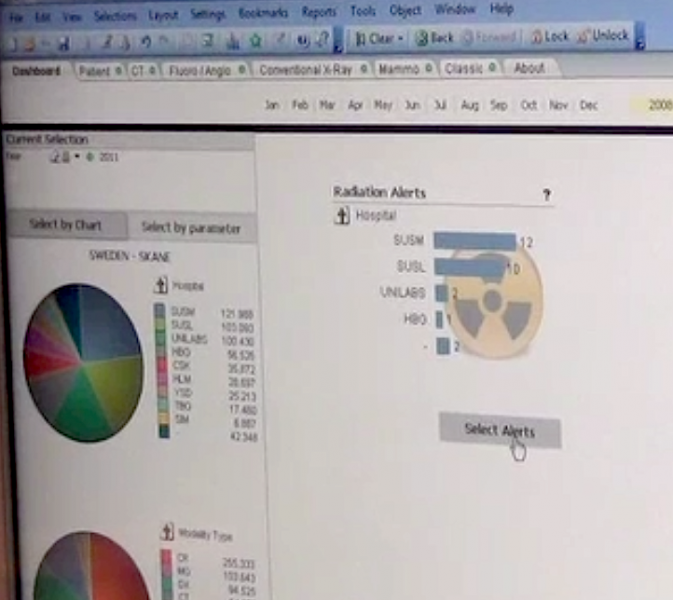

Patient X-ray radiation exposure from medical imaging has been a hot topic in radiology and has prompted the implementation of radiation dose monitoring systems. Prior to these systems, dose measurements either were not tracked or required manual calculation of dose based on scanner data in the DICOM headers.